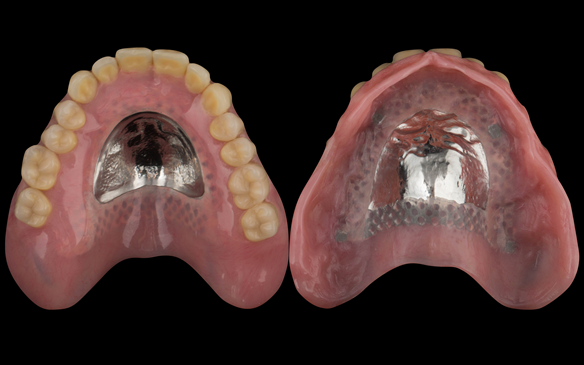

- Definitive dentures (Mk 2) – complete upper metal reinforced and lower cobalt chromium based partial of hygienic Scandinavian design to be made 9 - 12 months after extractions of all upper teeth and LR5 and LL4

The clinical situation and treatment process is shown in detail below with photographs.

The patient has been successfully rehabilitated and is now having periodontal maintenance from Syed Abad, Specialist in Periodontics at the practice. His quality of life has improved considerably. The clinical prosthodontics was provided by me and the technical work by Rowan.